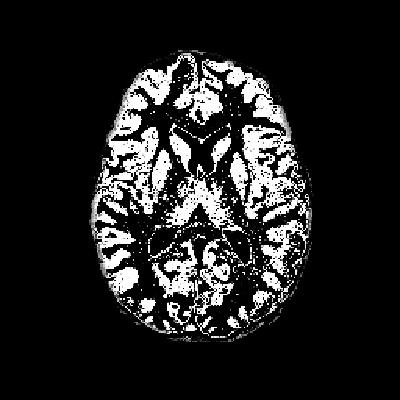

- 原始图像:如图1所示,原始图像中存在较多噪声,直接使用FCM算法进行分割会导致结果不准确。

从代码中可以看出,我们首先加载了一个.mat格式的数据文件,其中包含了待处理的图像img和掩膜图像mask。掩膜图像的作用是指示图像中感兴趣区域的位置,从而帮助我们仅对目标区域进行分割,而忽略背景噪声。